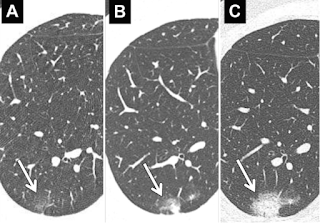

| Evoluția unui nodul pulmonar: A. la depistare; B. CT la 3 luni; C. CT la 6 luni. Sursa foto: Recommendations for the management of subsolid pulmonary nodules detected at CT: a statement from the Fleischner Society. |

- crește semnificativ în dimensiuni la CT-ul de urmarire în câteva luni